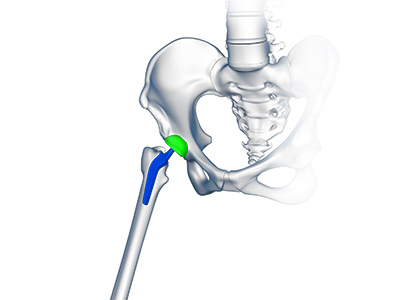

Robotic Assisted Hip Replacement Total Hip Replacement

Total Hip Replacement Outpatient Hip Replacement

Outpatient Hip Replacement Revision Hip Replacement